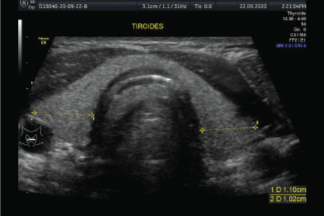

Una biopsia con aguja fina de un nódulo tiroideo es un procedimiento sencillo y seguro. Generalmente la biopsia se hace guiada por ultrasonido para asegurar la colocación precisa de la aguja en el nódulo tiroideo. El procedimiento es menos invasivo que la biopsia quirúrgica, deja poco o nada de cicatriz, y no involucra la exposición a la radiación ionizante.